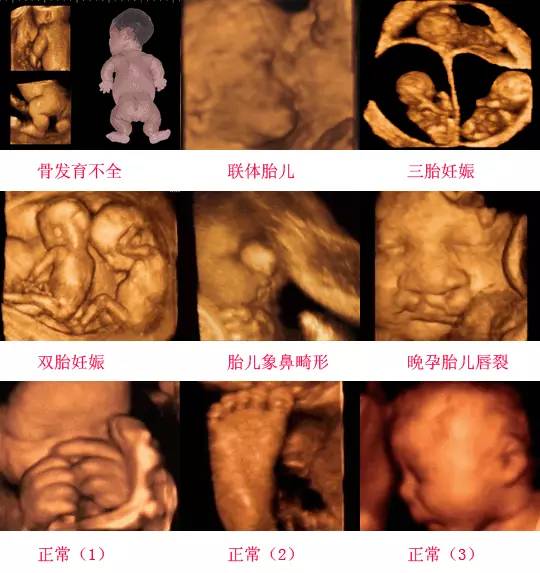

四維彩超是一種先進的醫(yī)學影像技術(shù),通過實時觀察胎兒在母體內(nèi)的活動情況,為醫(yī)生提供了豐富的診斷信息,在四維彩超下,我們可以清晰地觀察到胎兒的蛋蛋(睪丸)的形態(tài)、位置和大小等特征,胎兒蛋蛋是男性生殖系統(tǒng)的重要組成部分,對于胎兒的生長發(fā)育具有重要意義。

在四維彩超下,胎兒蛋蛋呈現(xiàn)出特定的形態(tài)和外觀,通常情況下,胎兒蛋蛋呈現(xiàn)出圓形或橢圓形,表面光滑,內(nèi)部回聲均勻,隨著胎兒的發(fā)育,蛋蛋會逐漸增大,并呈現(xiàn)出明顯的性別特征,醫(yī)生可以通過四維彩超技術(shù),對胎兒蛋蛋的大小、形態(tài)和位置進行評估,以判斷胎兒生殖系統(tǒng)的健康狀況。

四維彩超技術(shù)在評估胎兒蛋蛋發(fā)育方面具有重要意義,通過四維彩超,醫(yī)生可以實時觀察胎兒蛋蛋的形態(tài)、位置和大小等特征,了解胎兒生殖系統(tǒng)的發(fā)育情況,四維彩超還可以幫助醫(yī)生發(fā)現(xiàn)可能的異常情況,如睪丸未降、睪丸囊腫等,為及時采取治療措施提供依據(jù)。